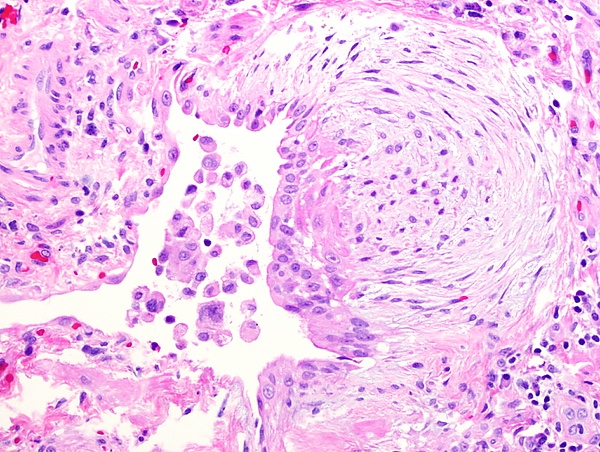

Фибробла́сты (от лат. fibra — волокно и др.-греч. βλάστη — росток) — клетки соединительной ткани организма, синтезирующие внеклеточный матрикс и коллаген[1]. Фибробласты секретируют предшественники белков коллагена и эластина, а также мукополисахариды. Фибробласты — самые распространенные клетки соединительной ткани у животных.

Форма фибробластов разнообразна, зависит от уровня их активности и нахождении в организме. Активные фибробласты увеличенного размера имеют отростки, овальное клеточное ядро, богаты рибосомами. Неактивные фибробласты (фиброциты) размером меньше, имеют веретенообразную форму.